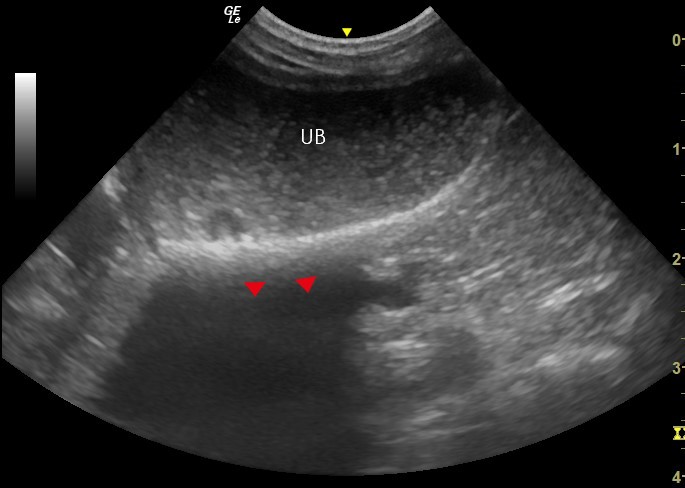

Similarly, agitating the fluid content by balloting the bladder will cause sediment to move or swirl within the lumen. Because free sediment will settle on the gravity dependant part of the bladder, imaging with the transducer positioned to view this area in the near field, or changing the patients position to cause sediment to shift, are techniques that can also be utilised to assist differentiation of artefact versus sediment present within the lumen of the bladder (Figure 4).

Figure 4. Bladder Sediment – This sagittal plane image of the bladder shows true sediment within the lumen of the urinary bladder (UB) as echogenic particles. The sediment has settled on the gravity dependent wall of the bladder, leading to the appearance of a relative thickening of the ventral wall of the bladder compared to the dorsal wall.5 Note the anechoic shadow (arrow heads) in the far field, deep to the sediment, which is caused by a lack of ultrasound waves propagating to the deeper structures. In this case, the acoustic shadow aids the diagnosis of abnormal, mineralised bladder content. However, not all luminal sediment will cause an acoustic shadow in this way.

Because the fluid content of the bladder is minimally attenuating to ultrasound, the tissue deep to the bladder will appear hyperechoic as a result of the ultrasound waves arriving to that area with more energy. This is known as distal acoustic enhancement (Figure 3). Reducing the far field gain can help to differentiate normal from abnormal.